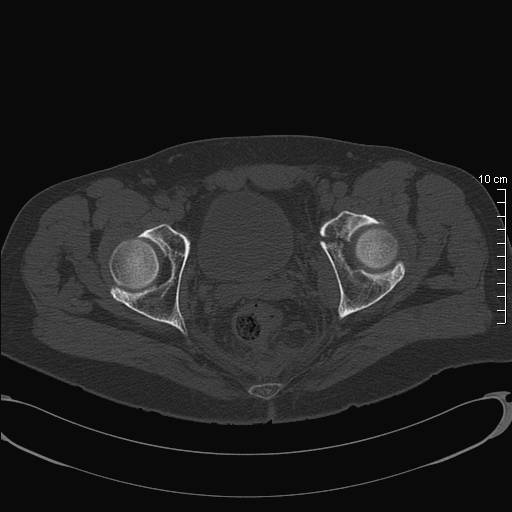

Перелом таза

Мужчина 54 года, рост 176, вес 84, упал, катаясь на лыжах.

по столь скудной визуальной информации можно лишь сказать, что видно повреждение передней колонны вертлужой впадины. Так что если есть еще и перелом именно таза, то надо обзорный снимок + inlet+ outlet. Если это все-таки ацетабулярный перелом - то прямой снимок и косые проекции (Judet).

фас, inlet, Judet, иначе не разобраться